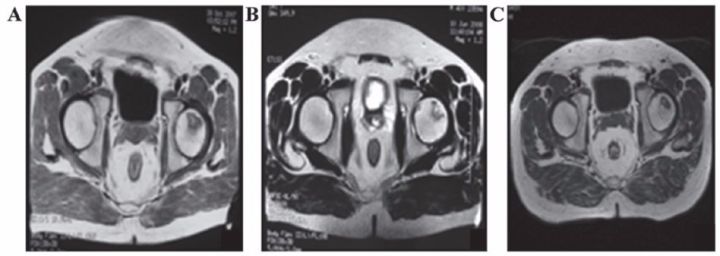

8、泌尿生殖系統(tǒng)疾病

?不孕不育

子宮內(nèi)膜受損嚴重,是很多不孕不育女性的噩夢。現(xiàn)在通過間充質(zhì)干細胞再生技術(shù)修復(fù)子宮內(nèi)膜,可重圓女性的母親夢。

南京鼓樓醫(yī)院婦產(chǎn)科胡婭莉教授團隊與中國科學(xué)院遺傳與發(fā)育生物學(xué)研究所戴建武教授團隊聯(lián)手,首次在國際上成功研制出膠原支架復(fù)合間充質(zhì)干細胞的方法,結(jié)合傳統(tǒng)宮腔鏡技術(shù),實現(xiàn)了受損子宮內(nèi)膜的功能性修復(fù),幫助3名患者實現(xiàn)做媽媽的夢想。

江蘇鹽城的胡女士在31歲到34歲時,經(jīng)過三次自然流產(chǎn),因為流產(chǎn)清宮手術(shù),子宮腔嚴重粘連。南京鼓樓醫(yī)院利用間充質(zhì)干細胞8個月修復(fù)了她的子宮內(nèi)膜,使她成功懷孕,并于2014年7月17日誕下了國內(nèi)第一位“再生醫(yī)學(xué)寶寶”。